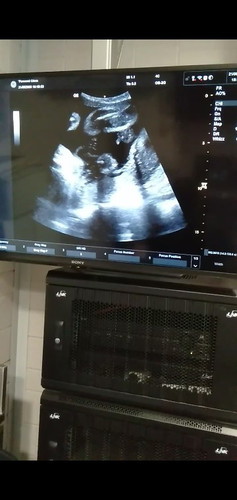

เพศชายมั้ยคะ

รูปนี้ใช้ ผช.มั้ยคะ อายุครรภ์ 27 w.ค่ะ